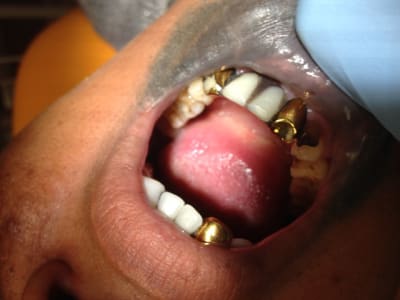

!

Img 0176 pwyr4q - Eugenol

Img 0177 irp4xh - Eugenol

Img 0178 uoinql - Eugenol

Img 0185 ve1nf0 - Eugenol

Et cela perdure depuis 20 ans...Patient CMU, veut changer les dents "jaunes" uniquement, traducteur pour lui expliquer qu'on ne fait pas mieux dans notre beau pays et que cela durera encore 20 ans